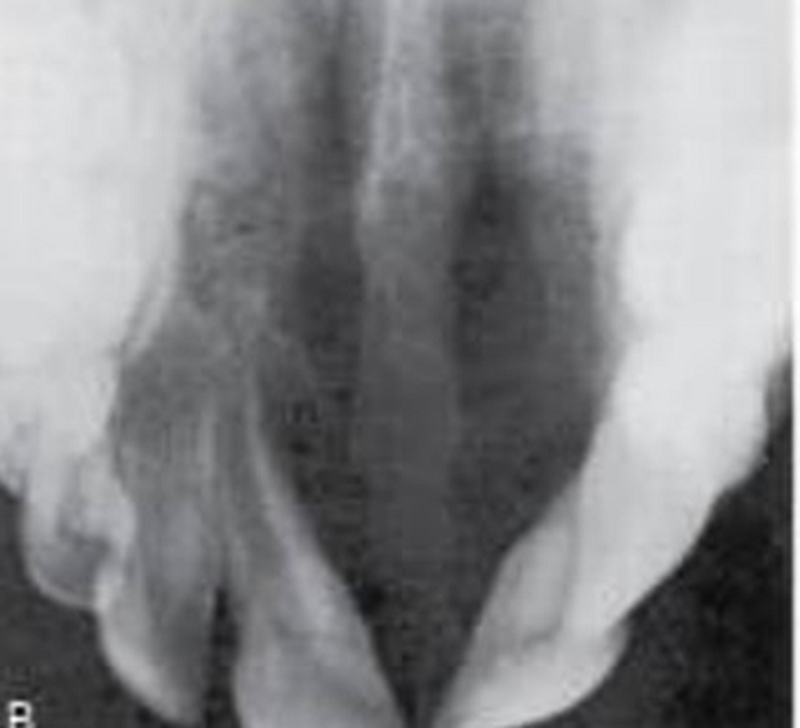

{"name":"Oral Path ID Chapter 6-9", "url":"https://www.quiz-maker.com/QPREVIEW","txt":"This condition is linked with Keratinosis of the palms of the hands & the soles of the feet. Individuals with this condition are likely to experience tooth mobility and premature tooth loss., This Term is used to describe The Appearance of type III (hypomaturation) Amelogenesis Imperfecta, Radiographs of a person with this condition appear to have a multilocular or “soap bubble” appearance","img":"https://www.quiz-maker.com/3012/CDN/92-4508546/final-pic-1.png?sz=1200"}